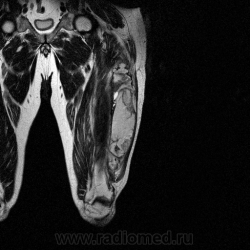

Добрый вечер Татьяна Валентиновна, можно и МРТ, а можно и результат гистологии, все по порядку, сейчас МРТ продемонстрирую.

Ну вот аксиальные срезы, где то затерял =(

С учетом вашего опыта, мне кажется Вам и без дословной интерпретации МР-протокола будет все понятно.

Мой коллега в заключении указал о вероятней всего рабдолейомиосаркоме, если я ошибся то чуть позже поправлюсь.

Я тоже пока что в этом деле лось, но думаю дело поправимое, на днях улетаю С-Петербуг в МАПО(цикл КТ и МРТ), ну да ладно, что косается пациента то он ещё в 2007 году обращался по месту жительства к травматологу по поводу ушиба бедра с формированием гематомы, была назначена местная рассасывающая терапия, до 2009г. видимо ждали пока рассасется в декабре обратился к хирургу по поводу посинения и увеличения в объёме задней поверхности бедра, назначен гепарин в феврале был вскрыт абсцесс в этом месте, далее только в марте сподхватились по УЗИ-мягких тканей признаки образования, ну и открытая ножевая биопсия: Описание изменений, выявленных при микроскопическом исследовании: в материале фрагменты опухоли, представленной пучками вытянутых клеток с полиморфными гиперхромными, местами уродливыми ядрами. Определяется значительное количество митозов, встречаются поля некроза опухоли. При иммуногистохимическом исследовании опухолевые клетки экспрессируют виментин, отсутствует реакция на десмин, гладко-мышечный актин, S100. Патоморфологическое заключение: саркома мягких тканей, боее вероятно фибросаркома.